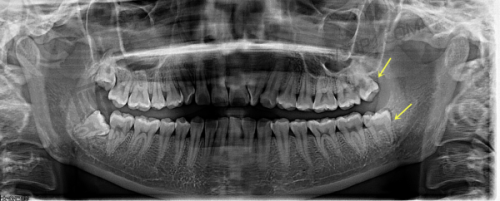

- 进口CBCT三维影像诊断设备——对牙槽骨、牙周等结构一览无遗